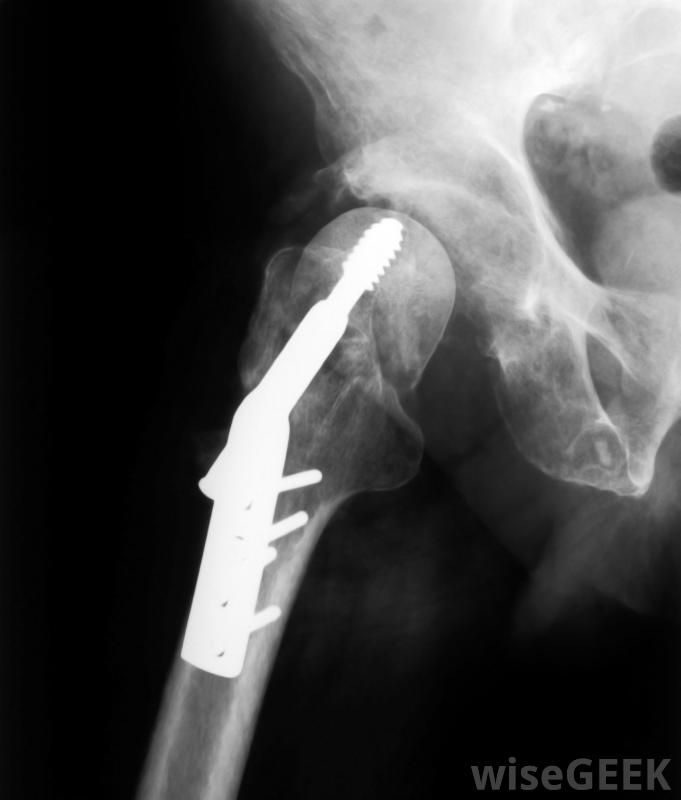

骨板是用来重建骨折骨的金属板。通常认为用于骨板的材料与人体相容。这样,钢板不会损伤人体,不会造成进一步的伤害,也不会引起机体产生免疫反应。最常用的骨板材料包括不锈钢、钴基合金、生物陶瓷、钛合金和纯钛。生物陶瓷是与人体相容的陶瓷,例如磷酸钙陶瓷。

钛板、螺钉和钛棒可用于骨折或其他损伤后重建骨骼或关节钢板并不总是被认为是一种理想的接骨板材料,因为钢板在一段时间后会失去张力。当这种情况发生时,损伤不再处于压缩状态,这会减缓愈合过程。钛板的使用时间会更长一些,但最终也会失去张力这是因为在设计接骨板时很难对骨折施加正确的压力而不会造成伤害,专家们一直在解决的一个问题。

放置骨板后,通常需要铸造和休息几个星期当需要使用骨板时,骨科医生会选择最适合的钢板,并将其固定在骨折两侧,钢板由螺钉固定到位,螺钉尽量放在离骨折处较远的孔中,以避免对已经受伤的骨头造成应力

骨板由螺钉固定。如果使用金属骨板来帮助稳定骨骼,则必须拆下一次骨头已经愈合。这需要额外的手术和恢复时间。移除金属骨板也会对骨骼造成额外的损伤,因为螺钉和钢板本身都会脱落。专家们正在研究用自然分解或被身体吸收的材料制成骨板,但是这种材料还没有金属板那样的强度,不应将骨板与体内自然形成的骨生长板混淆,骨生长板位于生长的长骨的两端,中间骨盖和骨干它们的目的是调节成熟骨的长度和形状。

金属销、钢板和螺钉可用于固定横向骨折。